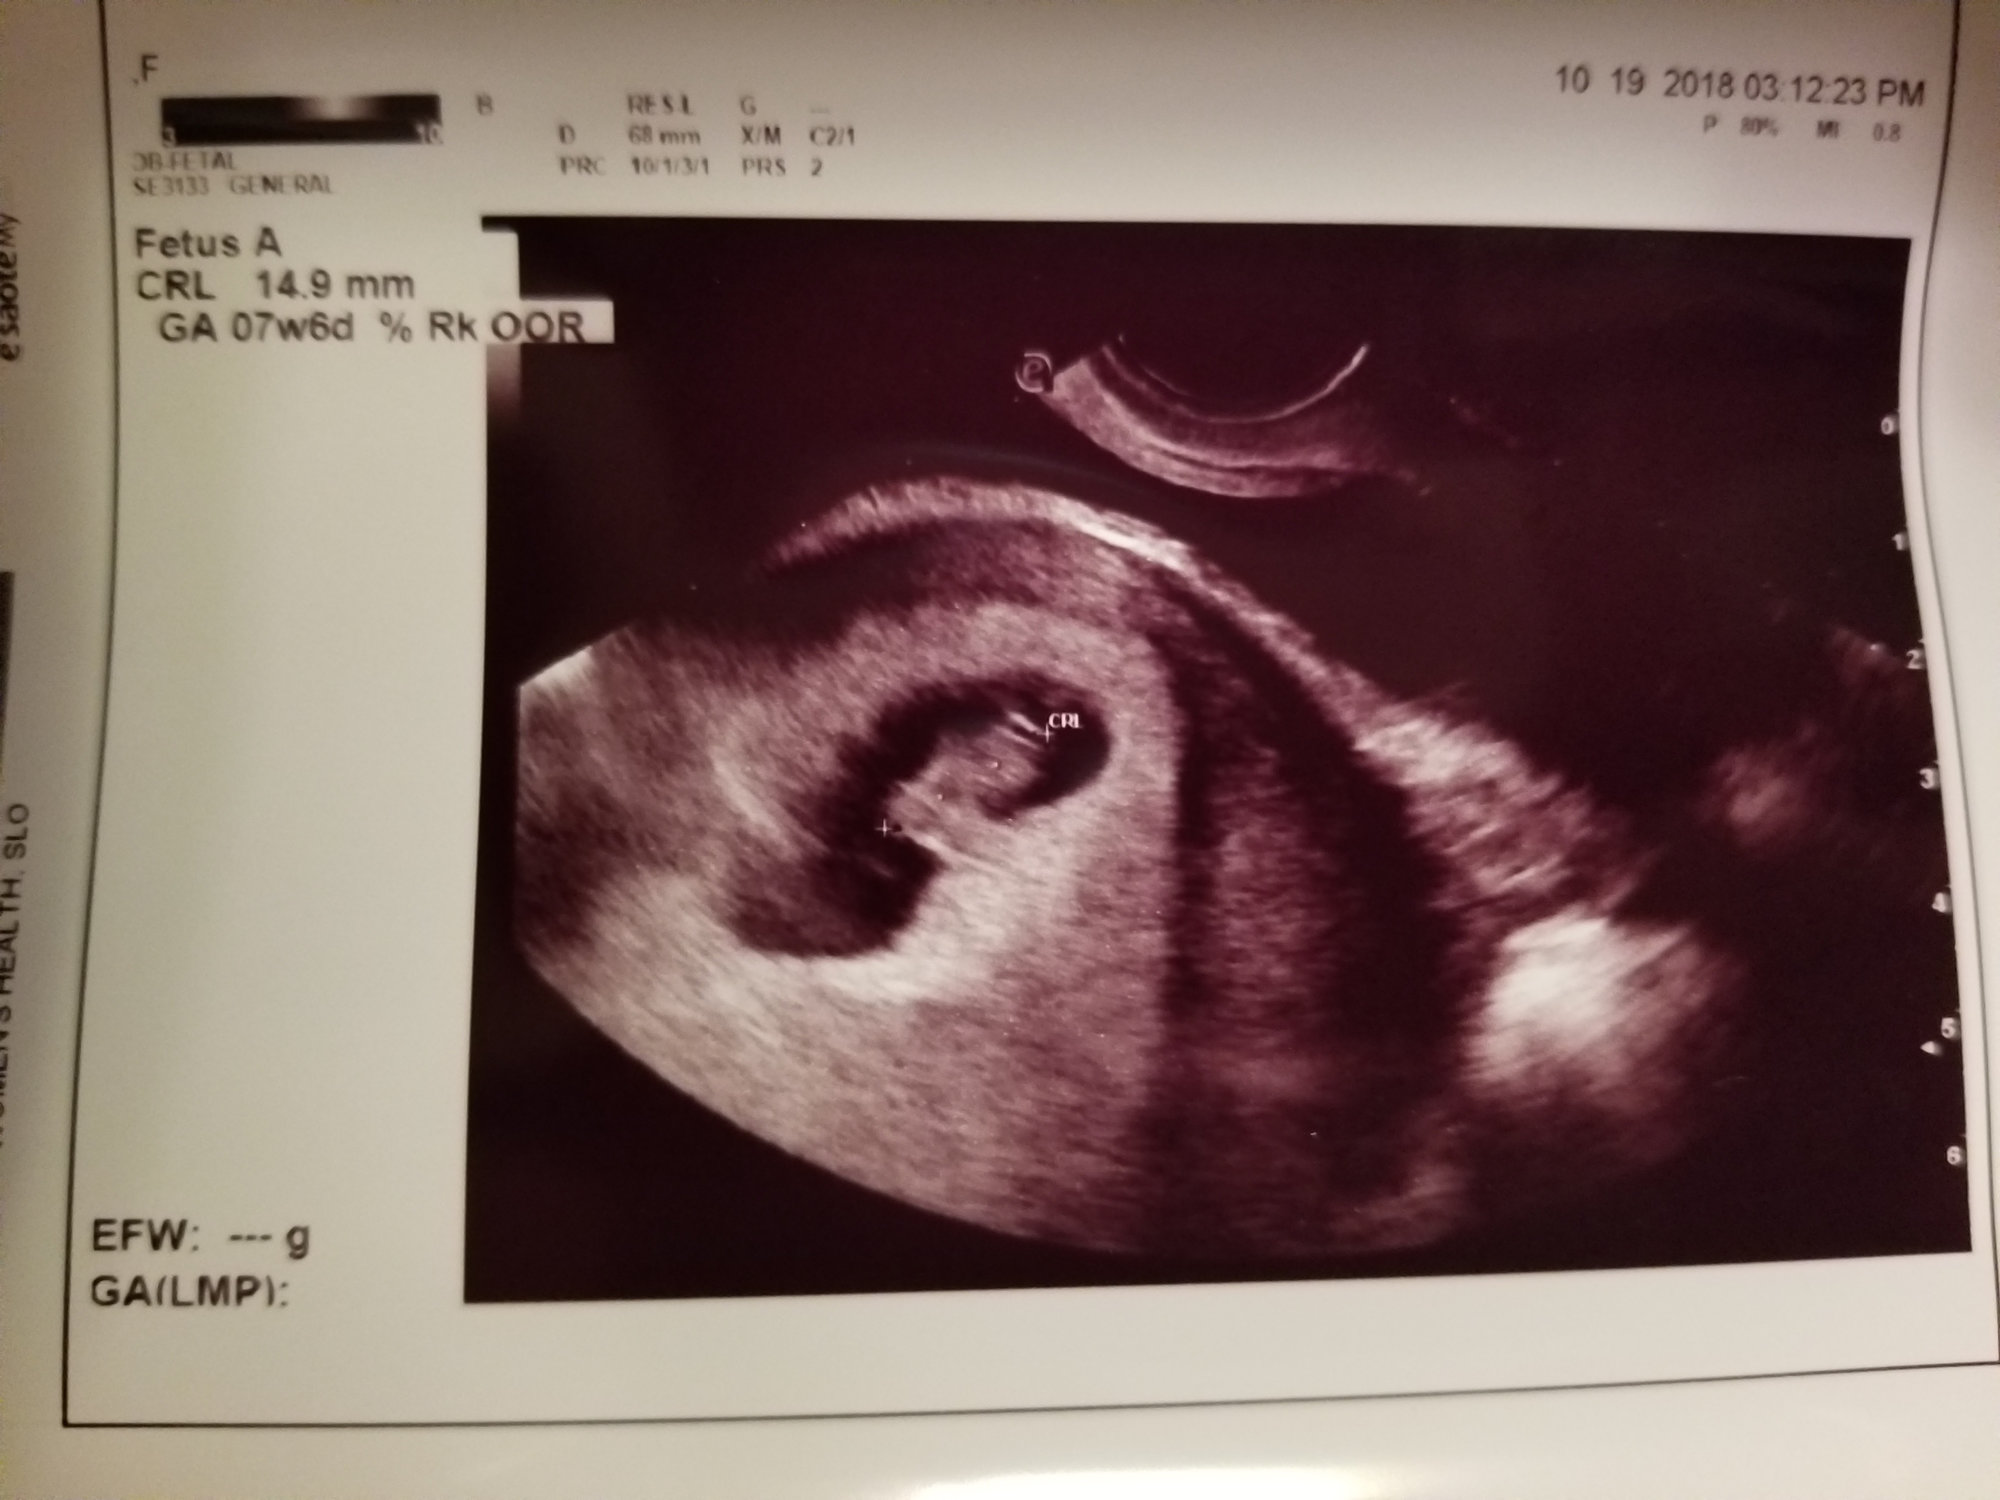

@mamajojo1981 this is the most adorable ultrasound!!